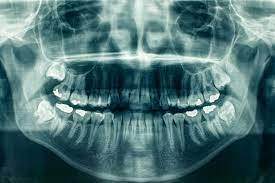

A tooth becomes impacted when there is not enough room to accommodate the space in the dental arch and growth becomes impossible. After surgery to remove an impacted tooth, mild discomfort and some swelling is expected. This is part of the process and should not alarm you. You may use cold compresses to alleviate the swelling. In addition, your doctor will prescribe pain medication, which should be taken as directed. Patients are also advised to favor the extraction area and modify their diet for a few days to allow for healing.